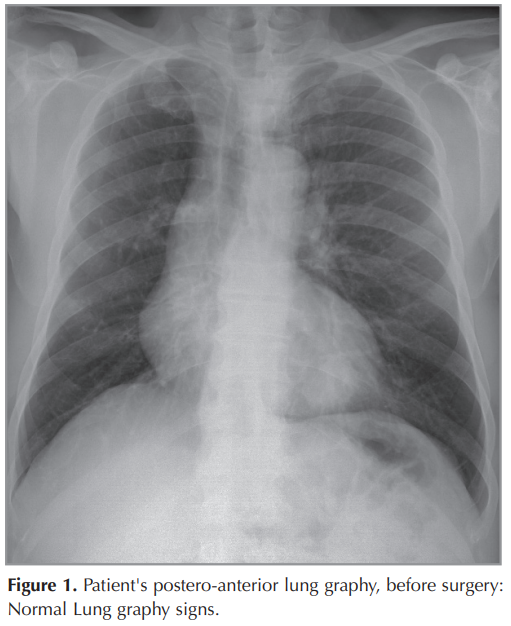

The patient is a 51-year old man, presented with shorthness of breath and cough for 1 months. Chest x-ray was normal (Figure 1). Chest CT scan showed a 30-25 mm heterogeneously enhanced mass lesion with well defined margin, In the left lower lobe of the lung (Figure 2). Bronchoscopy showed no endobronchial lesion. After the PET-CT, the patient was staged as cT2aN1M0 (Stage 2B) (Figure 3). He received video-assisted thoracoscopic surgery of left lower lobe of lung and mediastinal lymph nodes dissection ((Figure 4),(Figure 5)). His Ebv-Dna is Positive in blood tests. The pathology, immunohistochemical staining,and in situ hybridization results confirmed LELC of lung (Figure 6). Using in situ hybridization with exhibition of abundant EBV-encoded small nuclear RNA, in the majority of tumor cells is done. He received 4 cycles of induction chemotherapy with cysplatine and vinoralbine. The patient was discharged from hospital with close follow-up. No recurrence has been detected so far.

The patient is a 51-year old Turkish man, presented with shortness of breath and mild cough for 1 months. He has no chronic disease. Chest x-ray was normal (Figure 1). Chest CT scan showed a 30 × 25 mm heterogeneously enhanced mass lesion with well defined margin and lobulated contour, in the left lower lobe of the lung (Figure 2). Bronchoscopy showed no endobronchial lesion. Head and neck CT scan and nasopharyngeal fiberoscopy were performed and no obvious tumor was found. After the PET-CT, the patient was staged as cT2aN1M0 (Stage 2B), (Figure 3). He received video-assisted thoracoscopic surgery, of left lower lobe of the lung and mediastinal lymph nodes dissection ((Figure 4),(Figure 5)). His Ebv-Dna is Positive in blood tests. The pathology, immunohistochemical staining (Figure 6) and in situ hybridization results confirmed LELC of the lung. Using in situ hybridization with exhibition of abundant EBV-encoded small nuclear RNA, in the majority of tumor cells is done. Immunohistochemical staining was positive for cytokeratin (CK), a marker which was almost always positive in LELC of lung. He was discharged 10 days after the operation. He received 4 cycles of induction chemotherapy with cysplatine and vinoralbine. The patient had no postoperative complication and was discharged with the advice of chemotherapy. No recurrence has been detected so far.